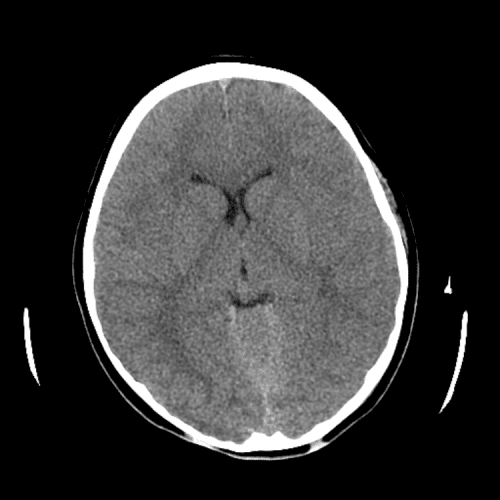

ACA and MCA territory infarct